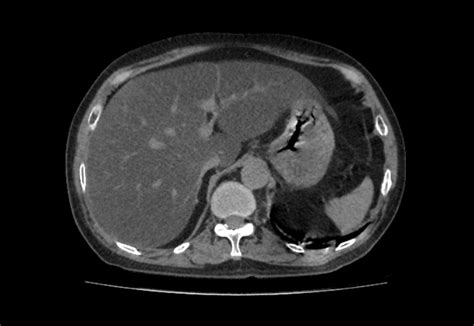

• Imaging Studies: Ultrasound, CT scans, or MRI can detect fat in the liver. A specialized ultrasound called FibroScan (elastography) is highly effective at measuring liver stiffness, which indicates scarring.